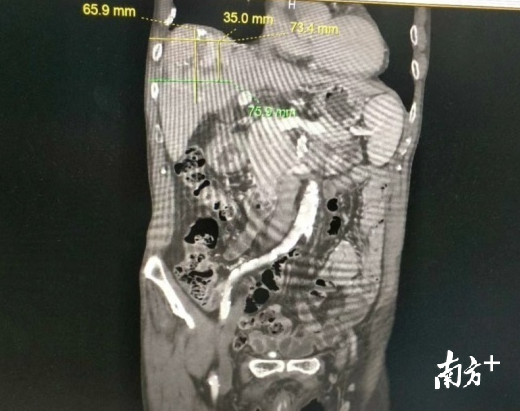

近日,中山七院肿瘤科就为81岁的黎先生实施了肝癌微波消融术。手术在CT引导下进行,短短20分钟时间,原先铅球大的肿瘤就全部被消融。术后,黎先生全身只留下一个小针眼,第二天就可以自由下地行走。据介绍,此次手术是中山七院肿瘤科与中山大学肿瘤防治中心联合开展的第2台介入手术,通过合作,中山七院肿瘤治疗有了“两把刷子”,为深圳患者提供更多治疗选择。

微波消融术是一种借助超声或CT等影像技术定位及引导,将微波消融针穿刺到肿瘤中心区域,释放微波磁场产生热量,使肿瘤组织高温坏死的微创介入手术,适用于肝、肺、肾、胰腺、前列腺等实体肿瘤。具有完全消融率高、原位复发低、并发症发生率低、安全可靠等优点。